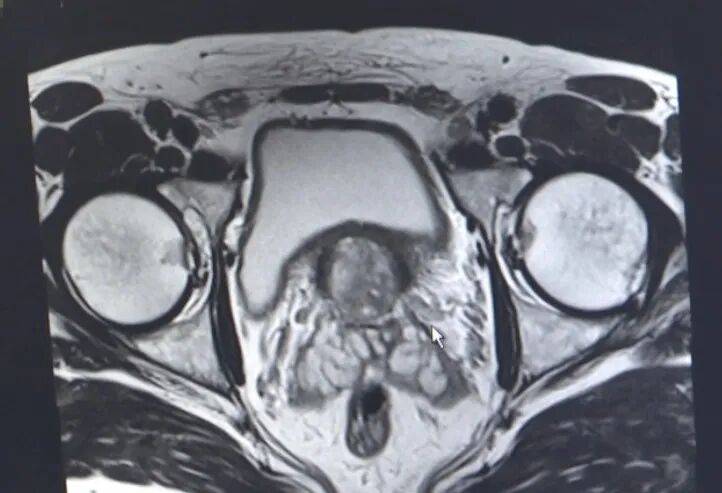

结合相关检查结果,泌尿外科科副主任庄乾锋建议进行前列腺穿刺活检,明确诊断,“ 前列腺癌好发于50岁以上男性,是男性泌尿生殖系统中最常见的恶性肿瘤,发病率在男性所有恶性肿瘤中位居第二。此病早期症状不明显,前列腺特异性抗原(PSA)升高提示前列腺癌风险高,但需行前列腺穿刺活检才能确诊。”

经穿刺后,龚先生被确诊为 早期前列腺癌,但没有转移,“虽然是早期,但我还是决定早点做手术,一院做达芬奇机器人手术已经6~7年,很成熟,因此我也很放心。”

专家介绍,前列腺癌手术十分精细、难度很大,不仅需要在盆腔狭小空间操作,而且周围血管非常丰富、解剖结构复杂,摘除前列腺后还需将尿道和膀胱精细吻合,对医生的技术要求非常高。 “达芬奇”机器人的机械臂关节可540度旋转操作,能快速完成暴露、分离、切割、止血、缝合及功能重建等操作,同时拥有高清3D成像技术,因此在此类手术中具有明显优势,可提供更精准的外科治疗。